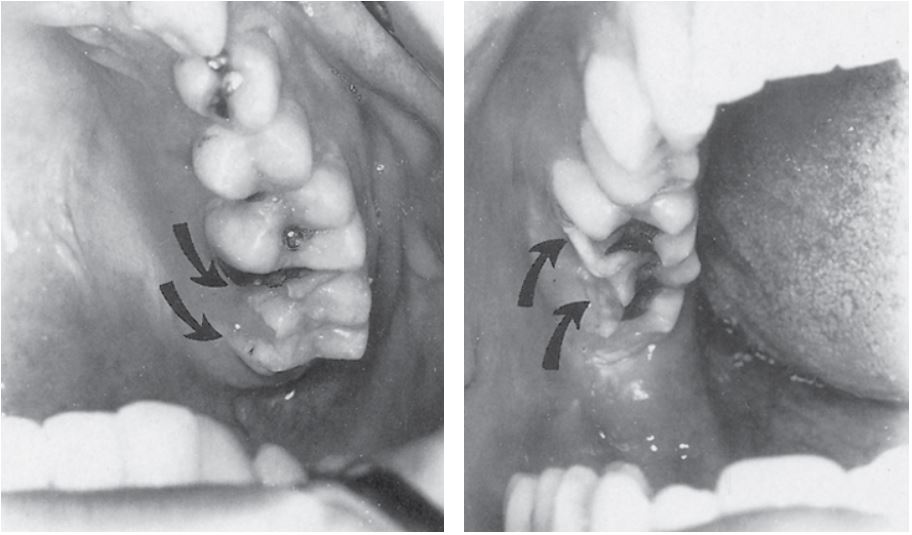

Ở các vùng phía sau, có thể xảy ra gãy múi ngoài hoặc múi trong răng cối nhỏ và răng cối lớn. Những đường gãy này thường kéo dài xuống phía dưới phần nướu dính và thường không lộ tủy (không biến chứng) (Hình 14.2).

Nguyên nhân của những chấn thương như vậy thường là do chấn thương gián tiếp.